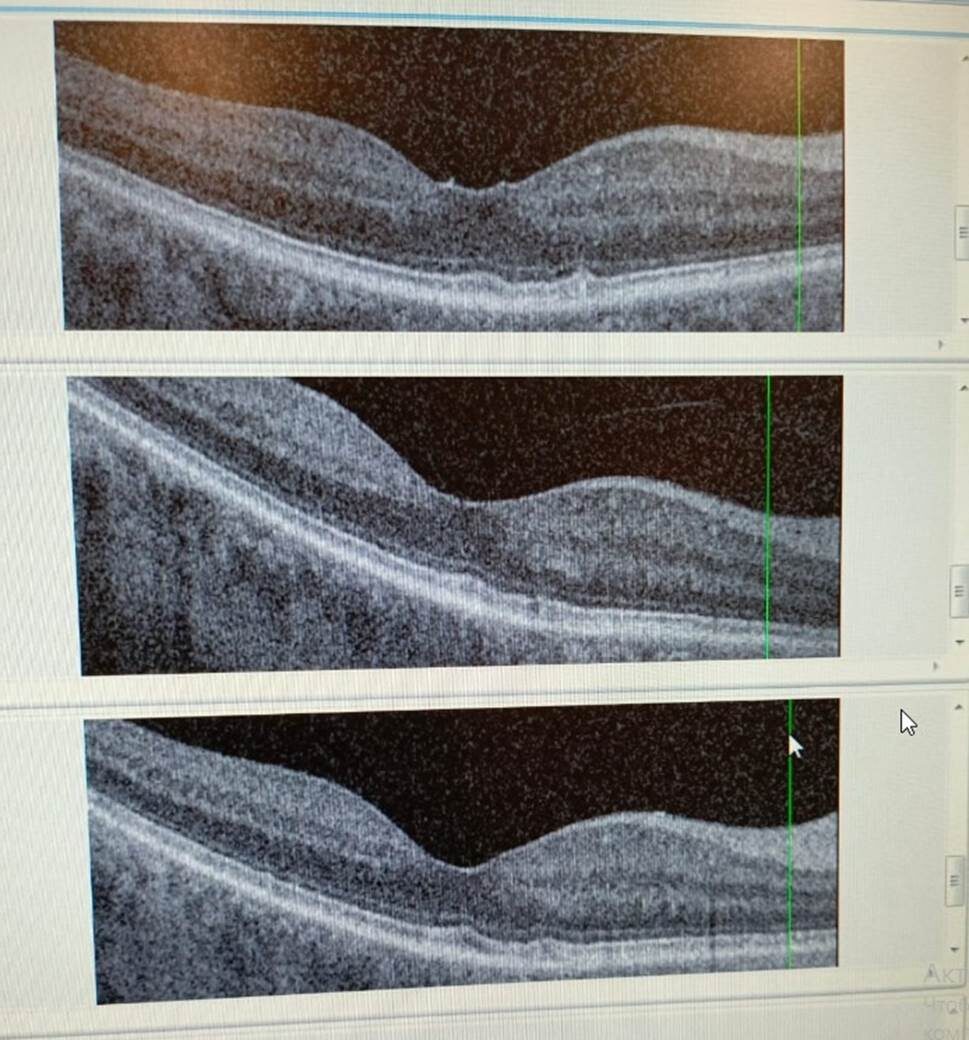

Рис. 1.Томограммы правого глаза пациента от 2 мая и 21 ноября 2023 года и 31 марта 2024 года (сверху вниз)

В центре верхней томограммы от 2 мая 2023 года на рисунке 1 видна зона натяжения, которая отсутствует через 6 месяцев на средней томограмме от 21 ноября 2023 года на фото 1. Поэтому заключение офтальмолога: Правый глаз (OD) - без натяжений, положительная динамика, сухие друзы пигментного эпителия, постинсультное уменьшение макулярной карты в верхней гемисфере OD. Врач, проводивший обследование затруднился объяснить произошедшие изменения, так как ранее с такой динамикой заболевания не сталкивался. Но, отметил, что другие признаки патологического процесса: «сухие друзы пигментного эпителия, постинсультное уменьшение макулярной карты в верхней гемисфере OD» - сохранились. На нижней томограмме от 31 марта 2024 года OD – уменьшение толщины макулярных карт с разрешением витреомакулярной адгезии в частичную отслойку задней гиалоидной мембраны. О сухих друзах пигментного эпителия офтальмолог не упоминает.